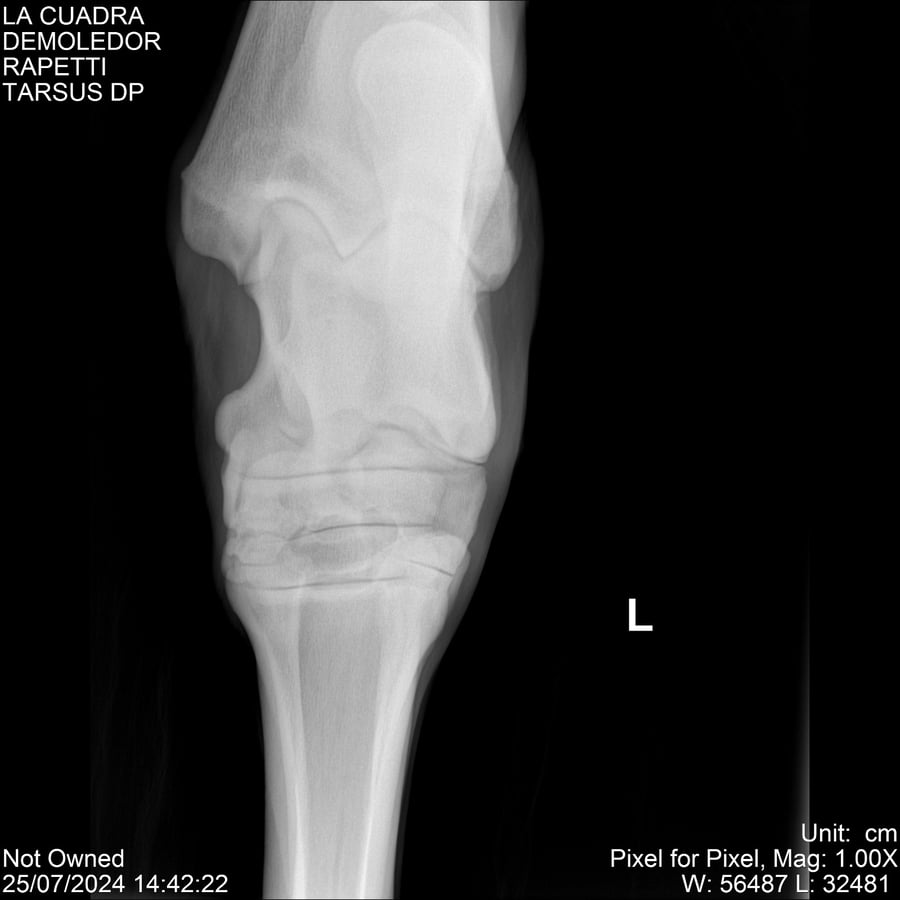

LOTE 14, DEMOLEDOR 🔥 🔥 🔥 Lote Anterior Volver al remate Lote Siguiente Ficha Contacto Montevideo - Ficha del Lote Identificador: #284454 Categoría: Yeguarizos Montevideo - 89 Visualizaciones ClicData Contacto Empresa: Abelenda N. R., Walter Hugo Nombre*: Teléfono* : E-mail* : Mensaje Enviar Registrese gratis Este contenido Exclusivo está disponible sólo para usuarios registrados Ingresar